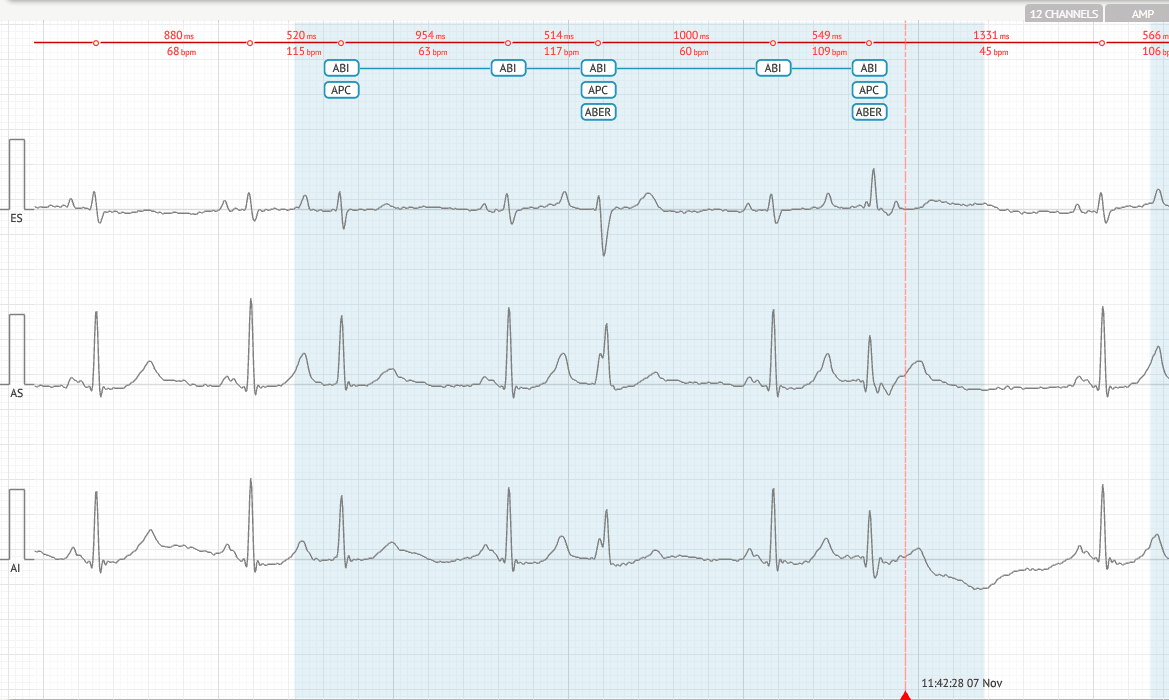

Atrial Bigeminy - (ABI)

Definīcija

Katram normālam sinusa sitienam seko priekškambaru priekšlaicīga sirdsdarbība (PAC).

Kritēriji

- Pēc katra normāla sitiena ir PAC.